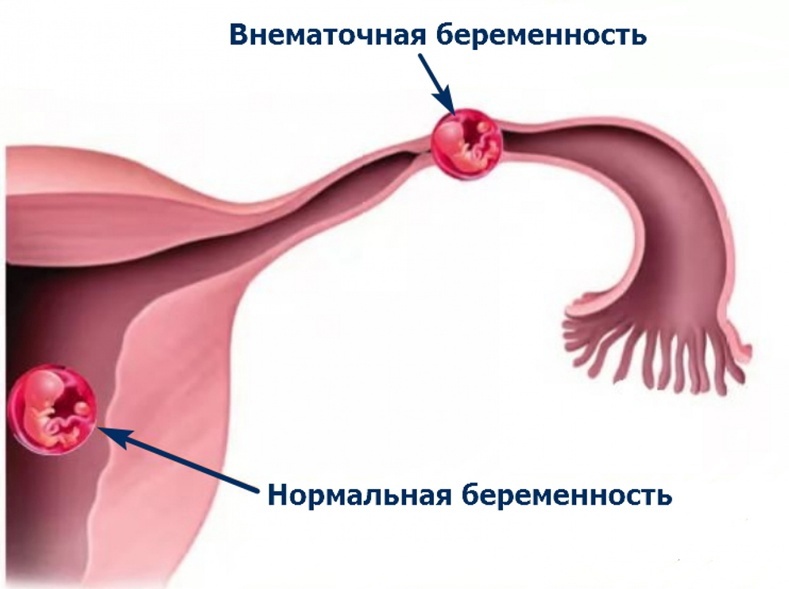

08.05.2024

Специалисты Больницы на Кутузова спасли пациентку с редкой формой внематочной беременности

15.08.2024

Успешное лечение гетеротопической беременности в КГБУЗ "КМКБ № 4"